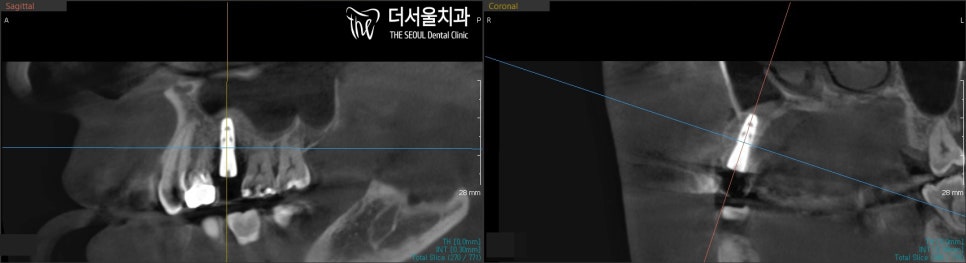

엑스레이와 CT 촬영을 통해

계획에 따라 잘 심어졌는지

꼼꼼히 체크합니다.

뼈이식과 픽스처는 잘 심어졌네요 ^^